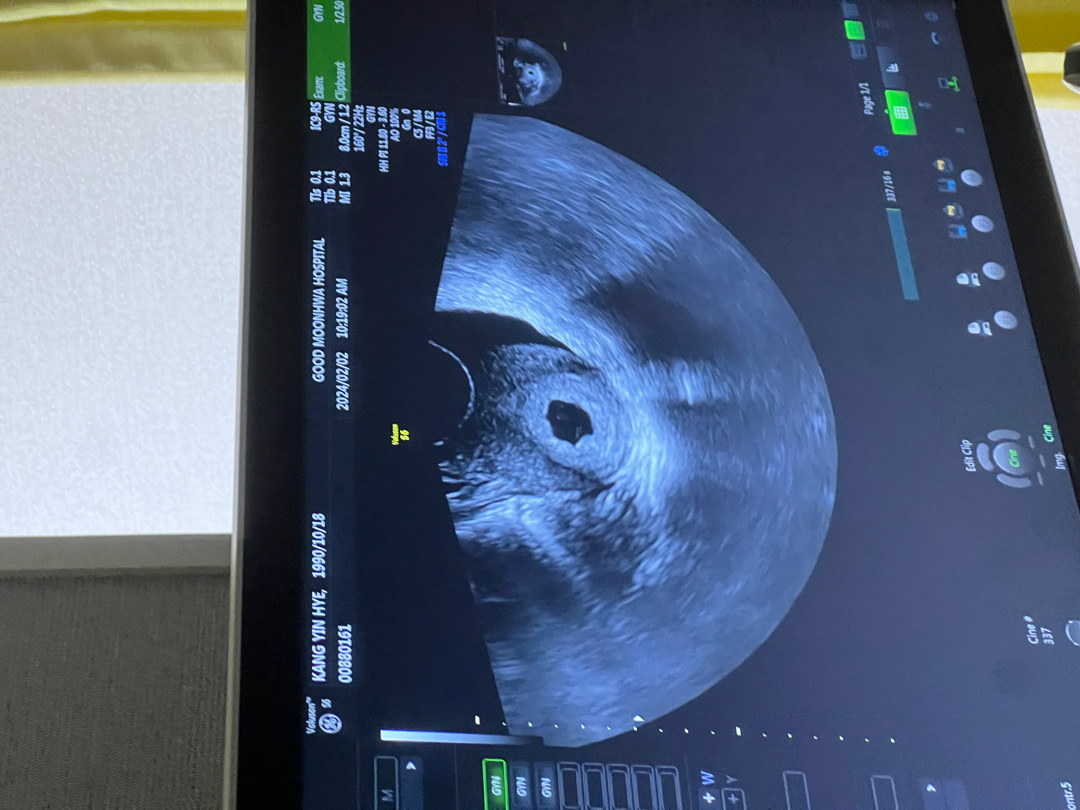

전 궁금한게 많은데 난임센터 의사샘은 별로 상세하게 이야기 안해주셔서.. 다음주부터 산부인과로 옮길겁니다.. 딱5주차 초음판데 혹시 애기집 크기가 1.2cm인걸까요?